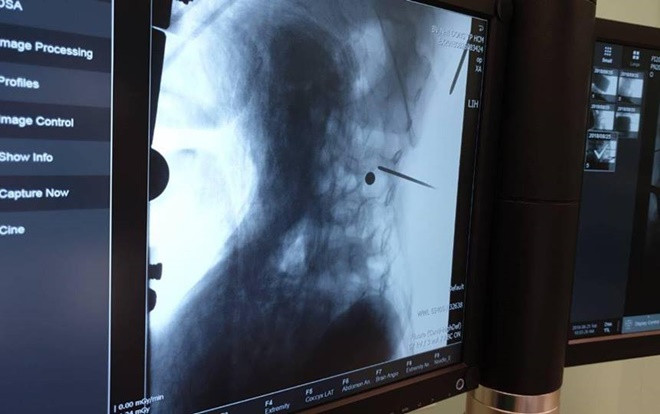

Ngay khi tiếp nhận bệnh nhân được chuyển thẳng lên phòng mổ sau khi đã đánh giá tổn thương và xem lại XQuang cẩn thận. Bệnh nhân được nhanh chóng mổ thám sát dưới sự hỗ trợ đắc lực của hệ thống C-Arm, hệ thống chụp Xquang tại phòng mổ.

Sau 1h làm việc hết sức, các bác sĩ đã lấy được viên đạn ra thành công. Được biết, nếu đạn đi chếch ra sau 1 chút sẽ đứt hệ thống cái rễ này, nguy cơ yếu liệt cao, nếu ra trước 1 chút sẽ đi xuyên qua bó mạch chủ ngay chỗ chia mạch chậu nguy hiểm tính mạng.